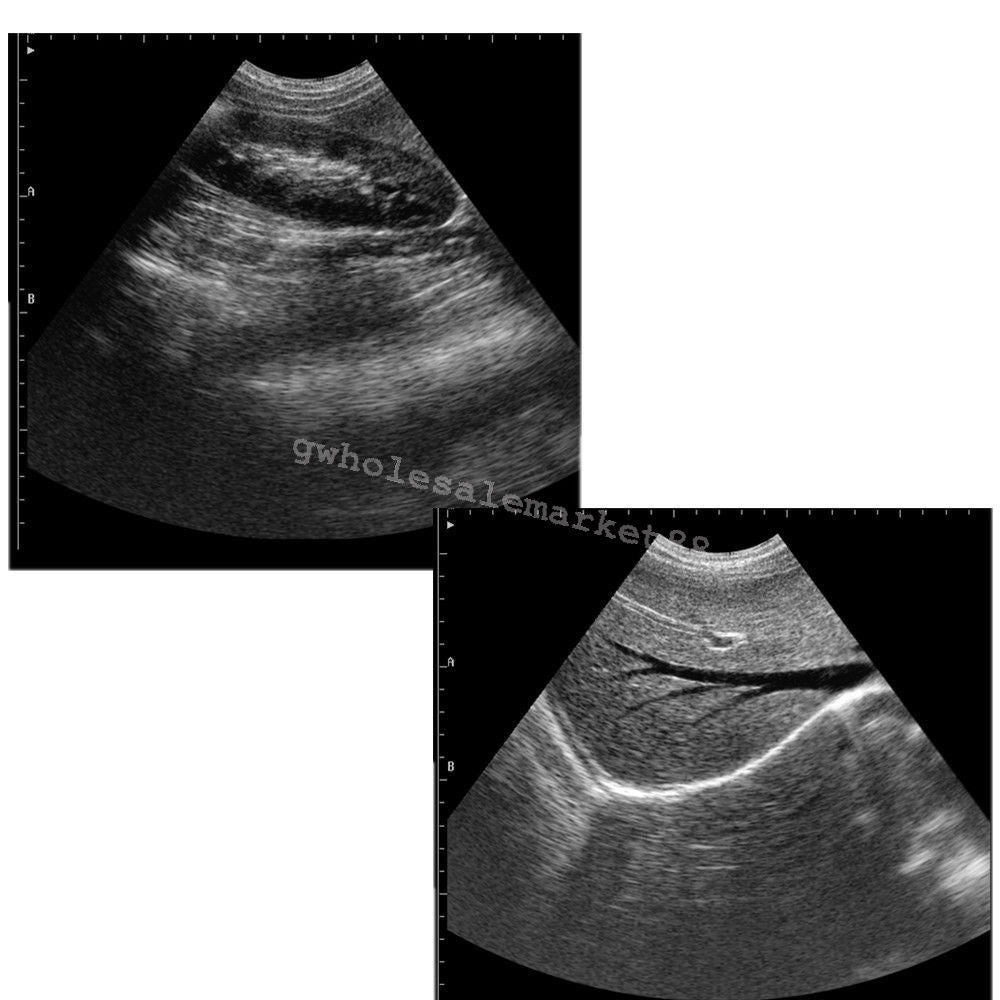

Versatile Functionality and High Precision

The laptop ultrasound scanner is designed for versatility and ease of use. It features both Convex and Transvaginal probes, allowing for comprehensive examinations in various settings. This scanner ensures high precision in imaging, giving healthcare providers the ability to make accurate diagnoses quickly. Because of its ergonomic design, it's easy for practitioners to operate, so they can achieve clear images with minimal effort.

Enhancing Patient Care with Advanced Technology

With the integration of cutting-edge technology, the laptop ultrasound scanner enhances overall patient care. It provides real-time imaging, which is crucial for timely decision-making. This means that doctors can evaluate conditions faster than with traditional methods. Moreover, as technology advances, this scanner will likely receive updates to improve functionality, making it an investment that continues to deliver value over time.